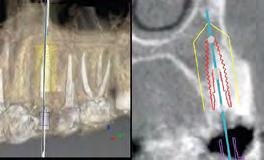

2. Image 2a: Pre-operative sagittal CBCT image demonstrating a Kan Class 1 sagittal root position with initial digital implant planning conducted during the consultation appointment. Image 2b: Definitive digital implant planning.

2. Pre-operative CBCT with virtually planned implant placement. A thin buccal plate (<1mm) is measured. Good apical bone is noted for the placement of a Straumann® 12mmx4.1mm bone level tapered implant.